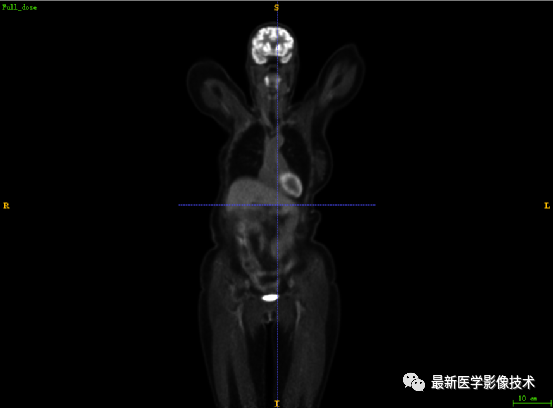

7.3、低剂量10重建结果

第一张是低剂量10的PET图像,第二张是full剂量PET图像,第三张是网络重建的PET图像。